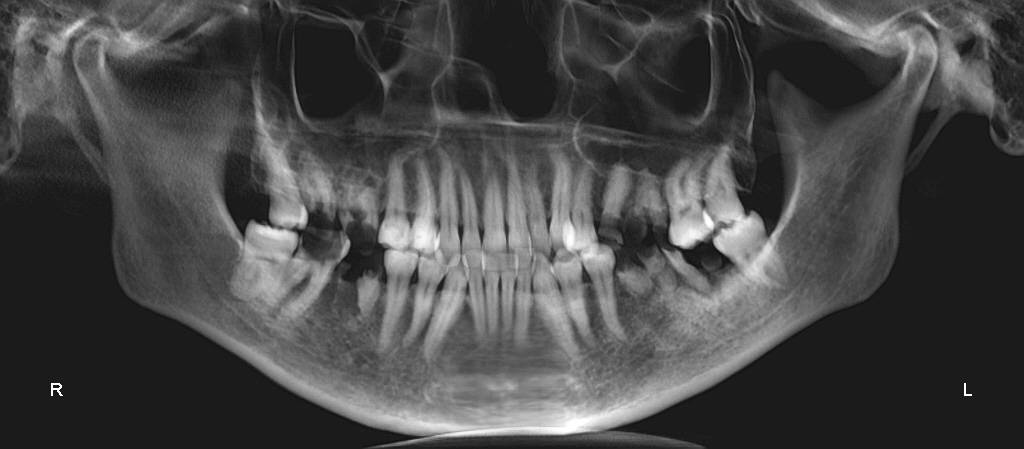

Девочки, кто сталкивался сориентируйте пожалуйста по ценам на взрослую стоматологию🙏 Объем работы большой, удаление восьми разрушенных зубов, удаление четырёх восьмёрок, синуслифтинг под один зуб, четыре импланта и всё это под наркозом... 550 000 норм? Или дорого?